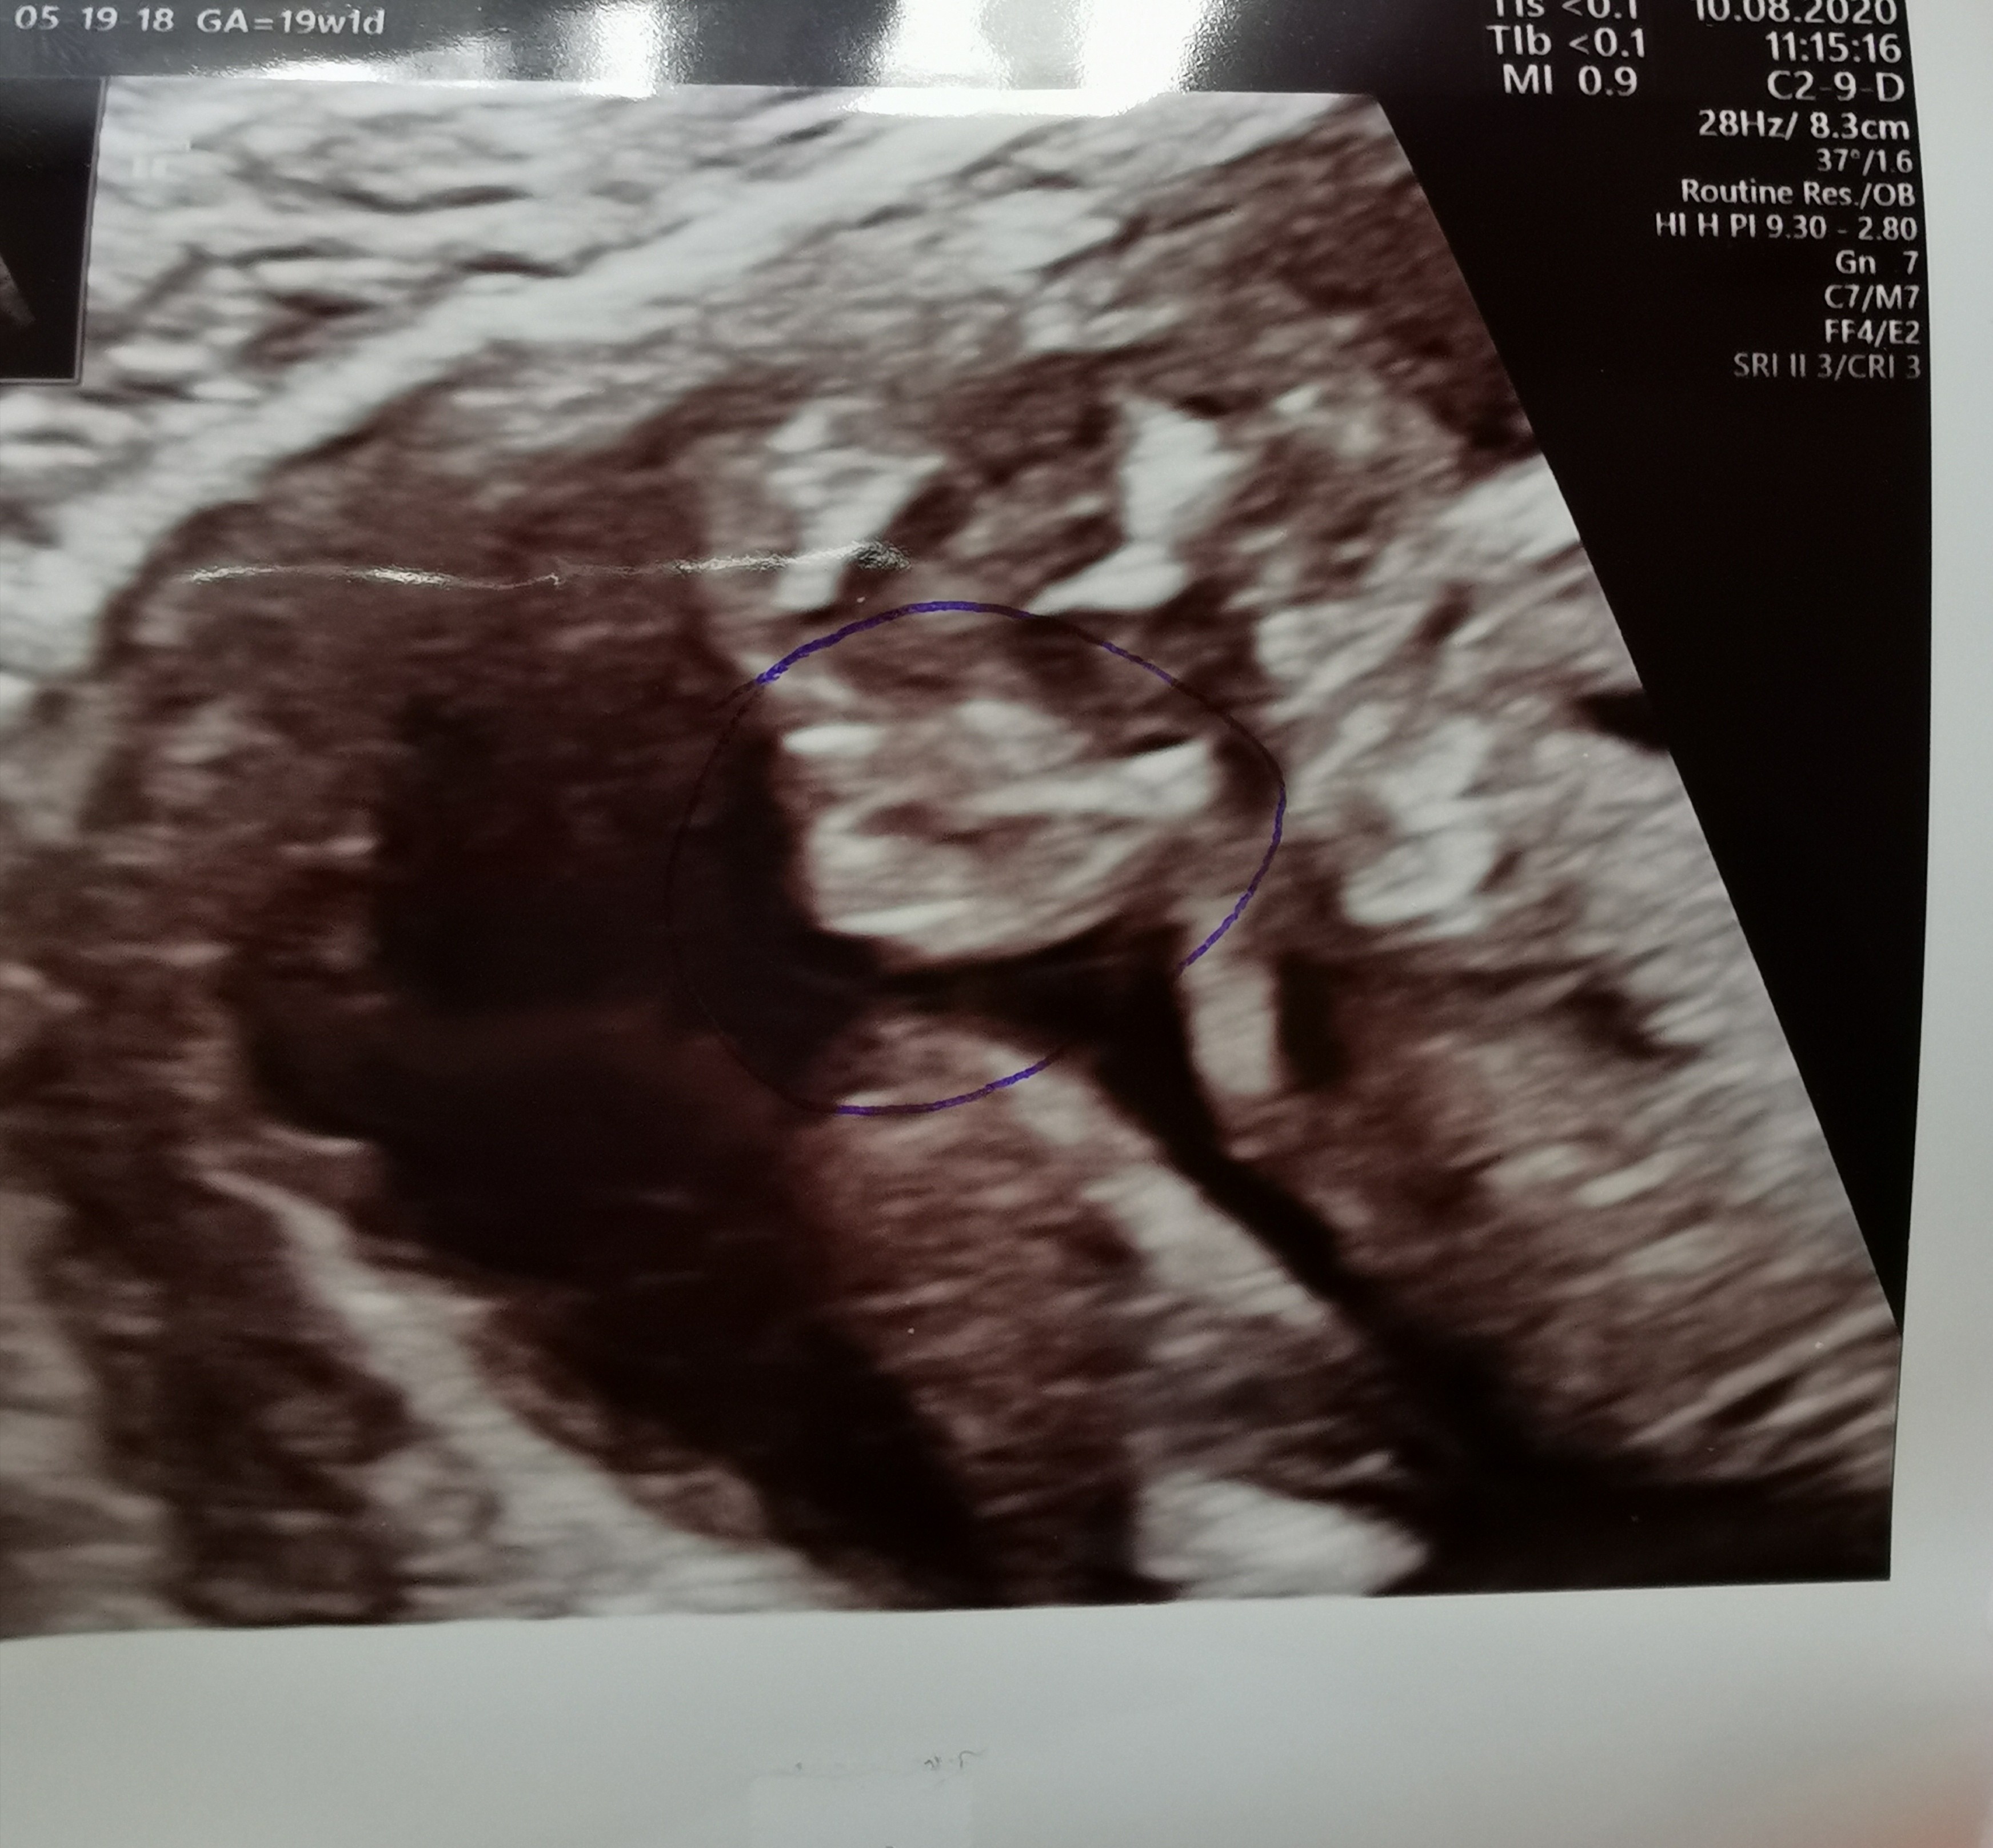

Witam w 19 tygodniu ciąży dowiedziałam się ze będę miała dziewczynkę w 20 tyg okazało się jednak , że to chłopak. Sama już nie wiem bo na jednym usg widać na pewno dziewuche a na drugim chłopca. Może to pempowina ?? Może ktoś mi pomoże rozwiązać ta zagadkę

• 4A8F5FF1-76CA-4DE0-AC12-5EDF08E820F2.jpg

596,4 KB · Wyświetleń: 44 121